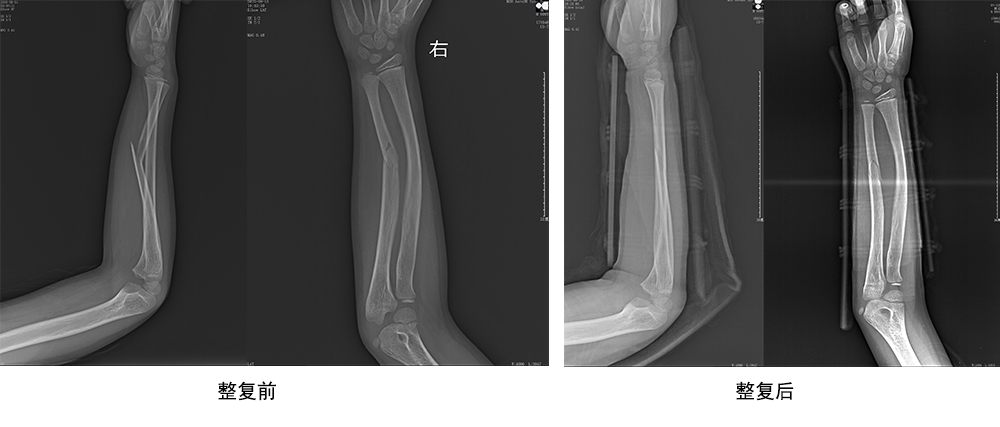

傳統(tǒng)手法整復(fù)病例影像

CR94676